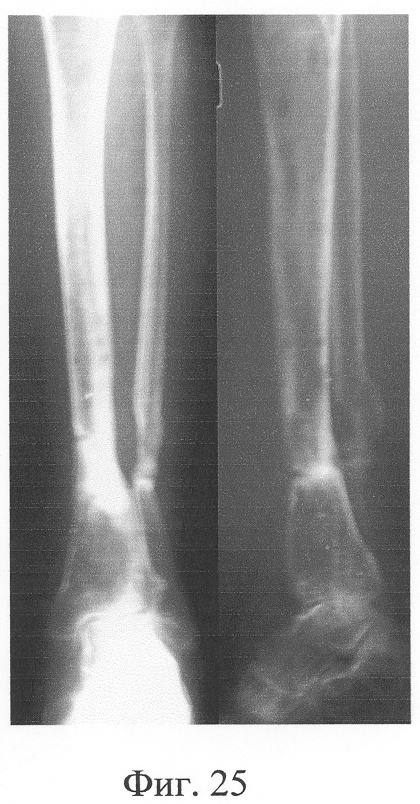

Аппарат внешней фиксации с левой голени демонтирован через 3 месяца после операции при клинико-рентгенологической картине сращения перелома. Аппарат внешней фиксации с правой голени демонтирован через 7 месяцев после операции при клинико-рентгенологической картине сращения перелома (фиг.20-25 – результат лечения). При рентгенологическом и томографическом контроле в трансплантатах отмечалось постепенное нарастание плотности костной ткани с формированием костной мозоли на всем протяжении между трансплантатом и костными фрагментами (фиг.26-29 – динамика данных компьютерной томографии правой голени: отмечается нарастание плотности костной ткани в области трансплантатов и формирование регенерата между смещенным трансплантатом и костными фрагментами; фиг.30-33 – динамика данных компьютерной томографии левой голени: отмечается нарастание плотности костной ткани в области трансплантатов и формирование регенерата между трансплантатом и костными фрагментами).